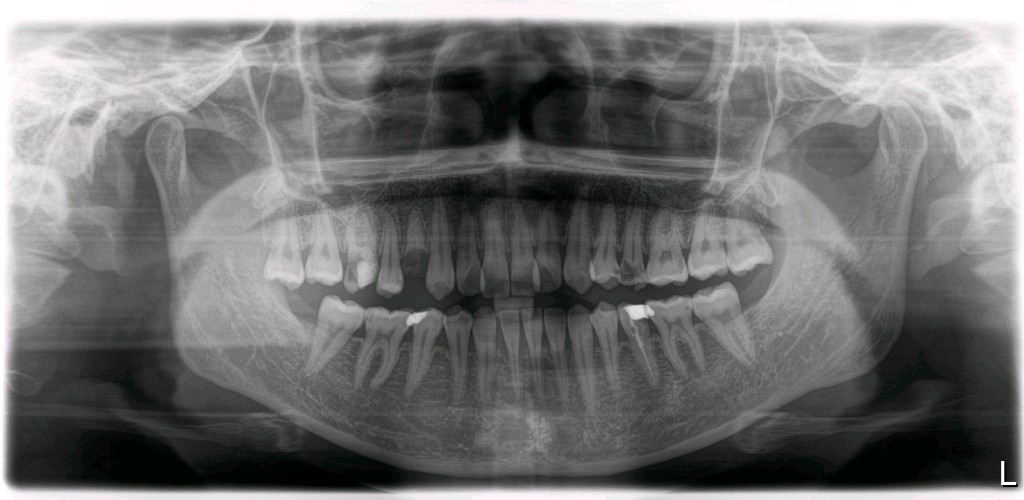

患者16牙体缺损,残根存,粘膜无红肿、出血,颌龈距离5mm,牙槽嵴丰满,。全口口腔卫生尚可,牙石(+),色素(+)。咬合、关节未见明显异常。 X 线示种植区骨密度良好